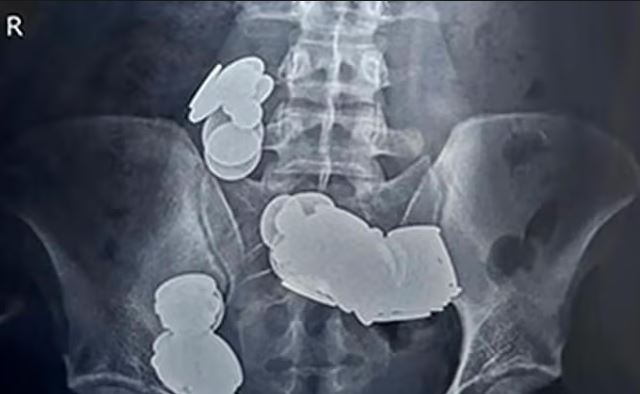

Moški iz New Delhija je, da bi hitreje prišel v vrhunsko formo – ukvarjal se je namreč z bodybuildingom – pogoltnil kar 39 kovancev in 37 magnetov.

Toda posledice so bile katastrofalne. Mladi Indijec je dobil hude bolečine v trebuhu in je večkrat bruhal. Zato je pomoč poiskal v bolnišnici, kjer so ga slikali z rentgenom, pisanje oe24 povzema bosanski N1. Ko so zdravniki videli, kaj se skriva v njegovem želodcu, jim je zastal dih.

Kovanci so se namreč zaradi magnetne sile zlepili skupaj, kar je povzročilo črevesno obstrukcijo. A na srečo se je za 26-letnika dobro končalo. Kirurgom je uspelo odstraniti vse kovance in magnete, pacient pa je po enem tednu lahko zapustil bolnišnico.